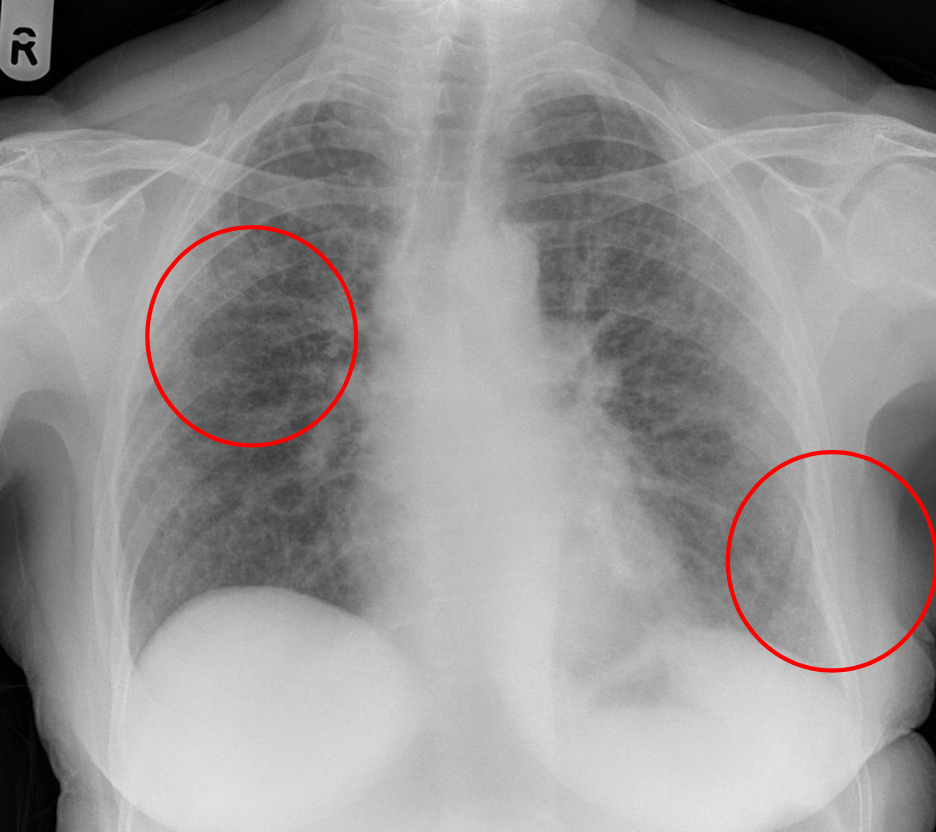

18

A

Patrón intersticial reticular

19

20

21